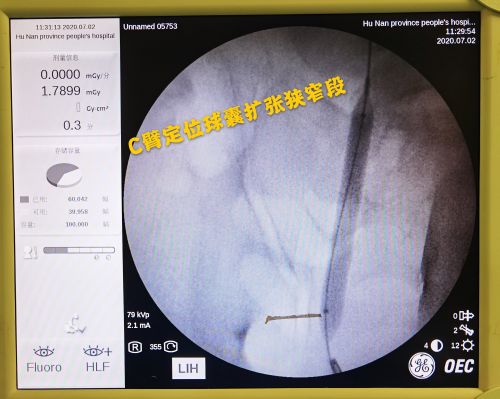

术中采用c臂机和造影剂精准定位狭窄段的近端和远端,并采用球囊扩张狭窄段,为腹膜支架的置入做足准备。

7月6日,段燚星主任医师、郭玺副主任医师、郭琼副主任医师等在全麻下,为患者施行“右侧输尿管镜检+右侧输尿管球囊扩张+右侧输尿管覆膜支架置入术”。手术分三步进行,首先通过输尿管镜找到狭窄段;然后用C臂机和输尿管球囊扩张(输入造影剂)精准定位狭窄段的近端和远端;最后在输尿管镜下完整置入Allium输尿管覆膜支架系统,同时在C臂定位下精准释放覆膜支架。